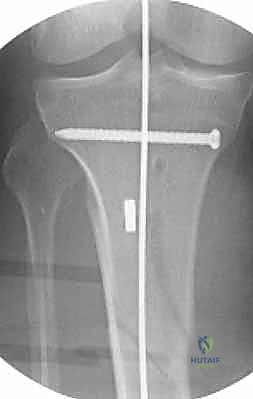

4. إدخال المسمار النخاعي والتثبيت النهائي

يتم تمرير مسمار التيتانيوم بدقة داخل العظم. وبمجرد التأكد من موضعه المثالي بالأشعة، يقوم البروفيسور هطيف بإدخال المسامير التشابكية (Locking Screws) العرضية في أعلى وأسفل المسمار لضمان التثبيت المطلق.

- التثبيت التشابكي (Interlocking): يتم تمرير مسامير صغيرة عرضية عبر العظم والمسمار النخاعي في الطرفين العلوي والسفلي، مما يمنع دوران العظم حول المسمار ويحافظ على طول الساق الطبيعي بدقة متناهية.